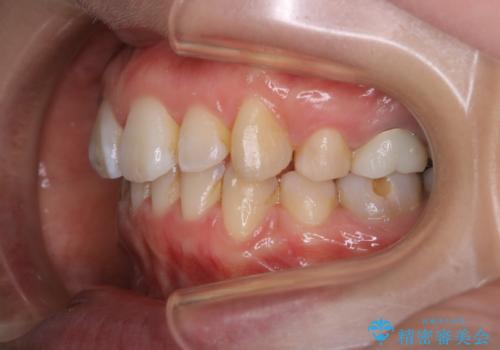

- 全体的に着色が付いているのが気になるとのことで来院されました。

PMTC60分コースを行いました。

着色がかなり頑固なため、エアフローも使い着色を除去していきました。

下の前歯にはかなり多くの歯石が付いており、デンタルフロスでもう少し防げるため、使用法や頻度を確認しました。

インビザラインの矯正治療は、マウスピースの使用時間が少ないとマウスピースと歯のフィッティングが悪くなりシュミレーション通りに歯が動かなくなるため、追加アライナーといって、再度スキャニングを行い新しいフィットの良いマウスピースに変えていきます。そのスキャニング時にアタッチメント(歯の表面に付いた突起)も除去するため、そのタイミングでクリーニングするのもおすすめです。